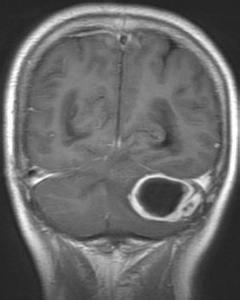

腦膿腫是腦組織內局限性積膿。耳源性腦膿腫是化膿性中耳乳突炎的嚴重併發症,重者危及生命,膿腫多發生於大腦顳葉,其次為小腦,發生於其他腦葉者甚少,膿腫一般為單發,多發並膿腫少見,致病菌以桿菌(如變形桿菌、綠膿桿菌等)為主,球菌則以金黃色葡萄球菌、溶血性鏈球菌較常見,亦有混合感染者。

1、顱腦CT掃描或MRI 可顯示農中的大小,位置、數目、腦室受壓等。而且安全無創。

鑑別診斷:注意和腦積水、腦腫瘤鑑別,耳源性腦積水分為交通性腦積水及梗阻性腦積水兩種,而以交通性腦積水多見,腦積水以顱內壓增高為主要症狀,全身症狀較輕,無局灶性症狀,顱腦CT掃描或MRI可資鑑別,腦腫瘤發展緩慢,無化膿性中耳炎病史及顱內感染症狀。